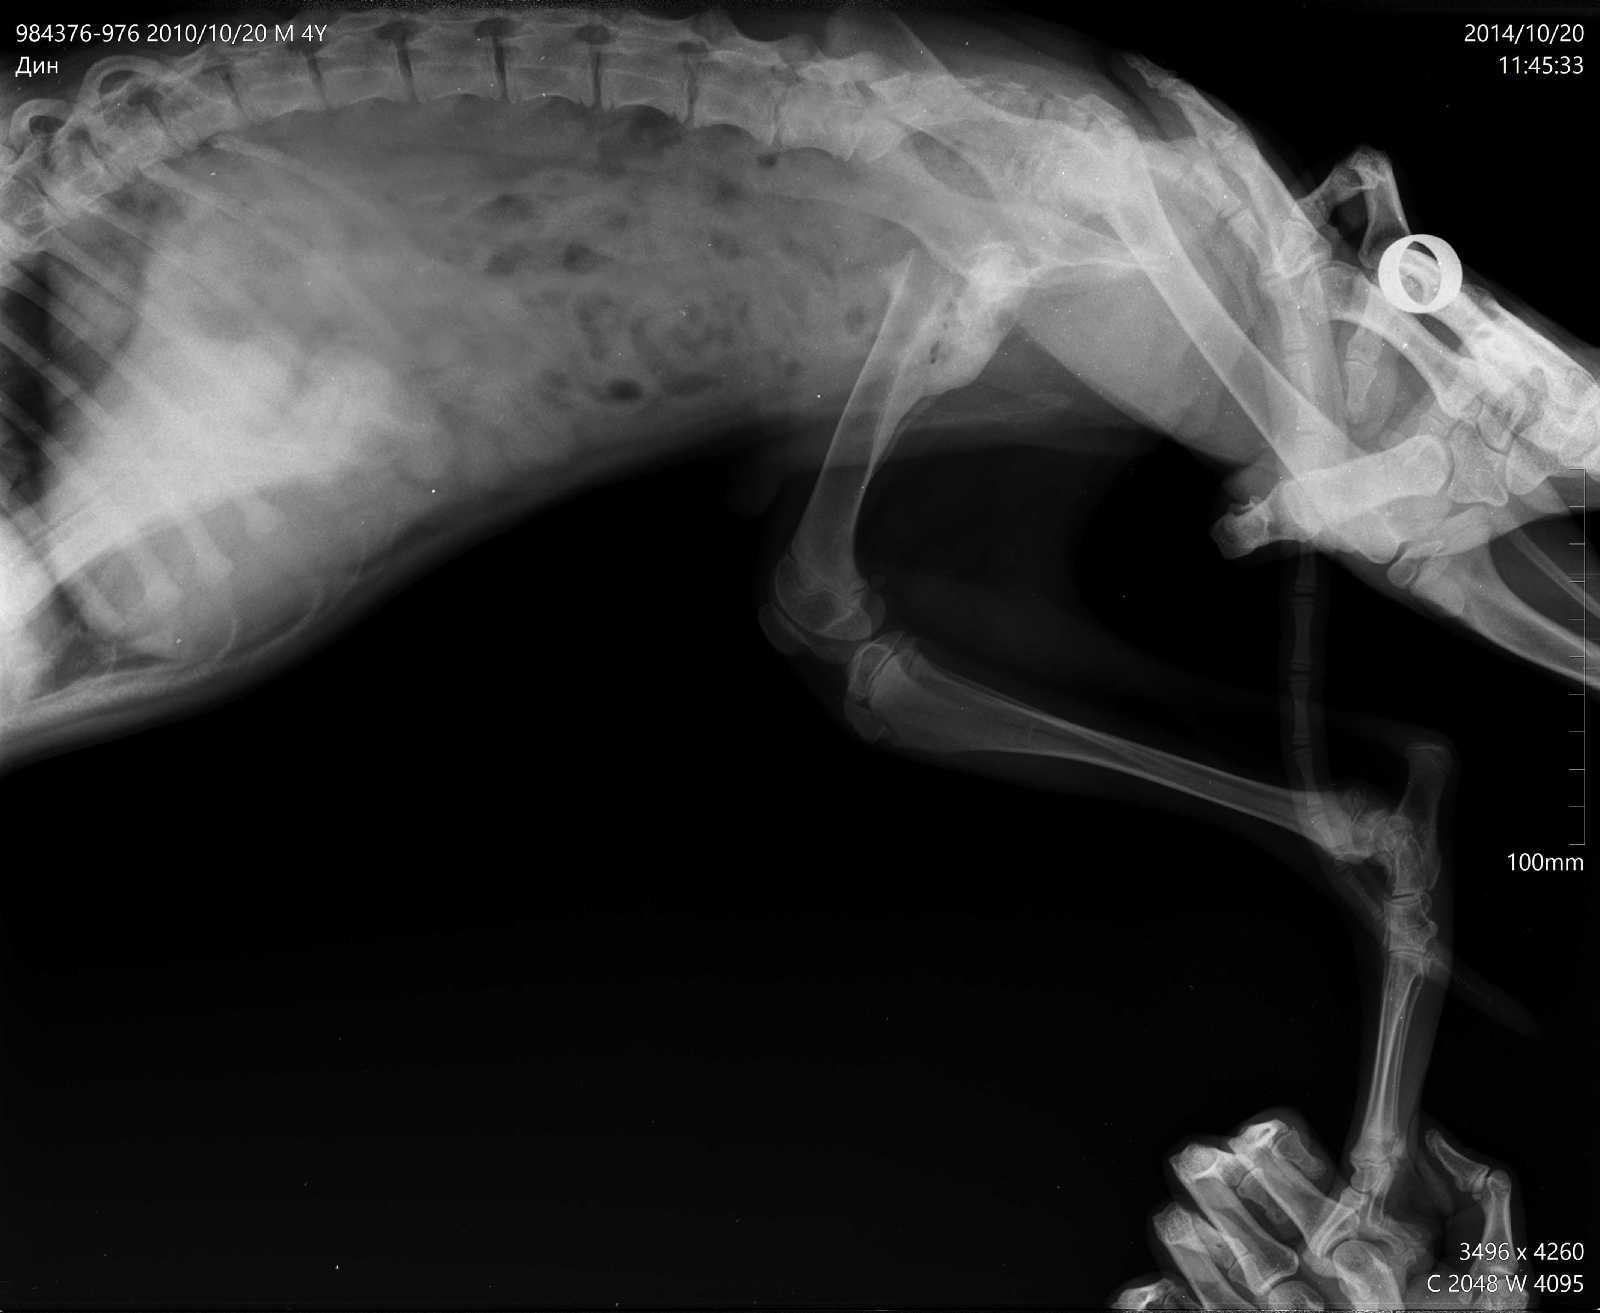

Болезнь Пертеса у собак (Болезнь Легга-Кальве-Пертеса) - симптомы ...

Болезнь Кальве Легга Пертеса у собаки: признаки, симптомы, лечение